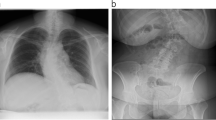

A 34 year-old women presented with acute cauda equina syndrome (loss of bladder and sphincter control, pain radiating to the S1 dermatome, genital hypoesthesia). The patient was pregnant (10 weeks of gestation). The MRI without contrast enhancing revealed a disk prolapse at the L5/S1 level (Fig. 1). The patient was scheduled for emergency surgery on the same day. The surgical treatment included a sequestrectomy via L5/S1 fenestration on the left side in prone position, duration of surgery was 88 min and anesthesia was balanced. No perioperative complications occurred and the patient gave birth to a healthy girl at 41 weeks (birth weight 4180 g). At 6 years’ follow-up, she remained free of symptoms and without neurological deficits.

A 39-year old patient presented at 33 weeks of gestation in the outpatient department with paresis of her left foot extension graded MRC 3/5 for 24 h and pain radiating to the left L5 dermatome due to a disk prolapse at L4/5 on the left side (Fig. 3). In two different hospitals, she was recommended for a surgical intervention after delivery. Due to the paresis of the left foot, the patient was advised to undergo urgent surgical therapy during pregnancy. She underwent a fenestration at L4/L5 on the left side with sequestrectomy (surgery duration 58 min, left lateral decubitus position, balanced anesthesia, intraoperative x-ray scan for verification of spine level). Postoperative CTG control was normal. Three weeks later, she delivered a healthy baby (birth weight 3030 g) without complications. After 14 months’ follow-up, no residual neurological deficits were present.